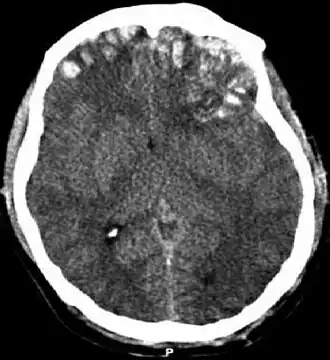

При проникающих и тупых черепно-мозговых травмах чаще применяется бесконтрастная КТ. Она обладает достаточной чувствительностью для обнаружения острого кровотечения и переломов черепа. КТ также позволяет оценить серьёзность травмы по показателю увеличенного внутричерепного давления, отёка мозга, дислокации мозга. Об угрожающем характере травмы могут свидетельствовать следующие данные КТ: смещение срединной структуры, сглаживание борозды, увеличенные или сжатые желудочки, потеря нормальной дифференциации серого и белого вещества. Всем детям с нарушением сознания, с показателем по шкале комы Глазго ниже 14, с проникающей травмой, с фокальным неврологическим дефицитом должна быть немедленно проведена компьютерная томография. Для оценки неочевидных для показания к КТ случаев травмы головы у детей применяются критерии малого риска черепно-мозговой травмы.

- Ушиб головного мозга: лёгкой, средней и тяжёлой степени (клинически). Ушиб головного мозга проявляется в ушибленной ране ткани мозга. Ушиб удар-противоудар наносится когда мозг ударяется о стенку черепа в месте непосредственного воздействия внешнего объекта на голову, получает одну ушибленную рану и затем ушибленная рана наносится на противоположную сторону мозга при резком замедлении движения ткани мозга. Клинические проявления зависят от расположения ушиба, и включают изменение психического состояния, повышенную сонливость, спутанность сознания, тревожное возбуждение. Небольшие интрапаренхиматозные кровоизлияния и припухлость окружающей ткани часто можно определить при компьютерной томографии.